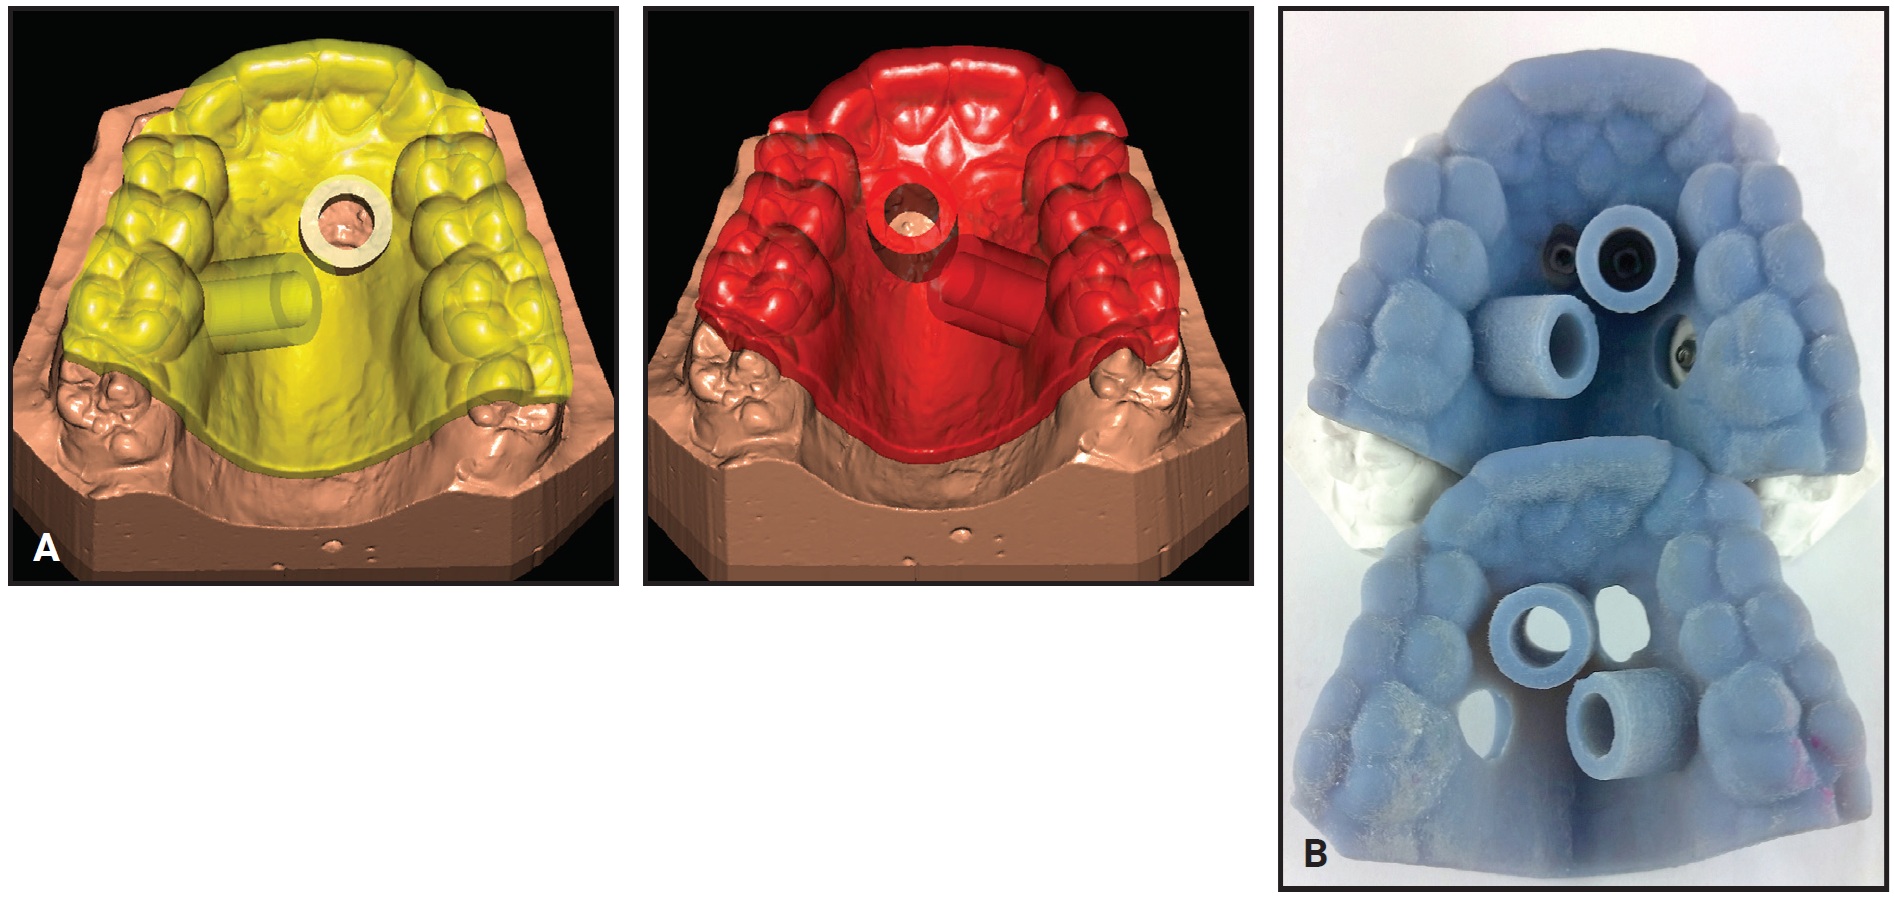

To identify the optimal sites for mini-implant placement, first obtain a stereolithographic (STL) file of the maxillary model. Using Easy Driver** software, identify three common points between the surface mesh and a CBCT image, then match the cross-sections of the digital model and the CBCT to produce an accurate superimposition. The software allows virtual planning and placement of TADs in a variety of lengths and diameters, according to the anatomical variations of each patient. Position the paramedian anterior TADs (usually 9mm in length and 2mm or 2.3mm in diameter) within the T-Zone. The posterior TADs (7mm or 9mm in length and 2mm or 2.3mm in diameter) can be inserted between the roots of the second premolars and first molars. The three-dimensional orientation of the CBCT ensures adequate space between the roots in an area of good bone quality.

The planned mini-implant positions are indicated by laboratory implant analogs, which are either inserted manually in the marked locations on a 3D-printed model or transferred to a plaster cast in the laboratory. Fabricate the Quadexpander on this model using a preformed jackscrew*** with an expansion capacity of 10mm. Weld the jackscrew to four preformed rings† on the laboratory analogs while bending the expansion arms to adapt them to the shape of the palate.

Digitally design the insertion guide around the mini-implant positions, and fabricate it from a biocompatible resin‡ in a 3D printer.†† Removable cylindrical sleeves are used to ensure precise coupling with the mini-implant driver for accurate insertion. At the chair, insert the selected mini-implants with an inner thread† through the placement guide using a contra-angle screwdriver. At the same appointment, attach the prefabricated Quadexpander to the four mini-implants with four fixation screws.†

Analysis of the CBCT image indicated sufficient bone for two 9mm × 2mm mini-implants† in the anterior palate lateral to the suture. Because the posterior paramedian bone was insufficient for skeletal anchorage, we decided to place two 7mm × 2mm mini-implants in the alveolar ridge between the roots of the second premolars and first molars. After overlaying the virtual model and the CBCT, the positions of the anterior and posterior mini-implants were digitally planned. The insertion guides were digitally produced (Fig. 3), and the mini-implants and Quadexpander were inserted at the same appointment (Fig. 4A,B).

Fig. 3 Case 1. A. Virtual design of two insertion guides. B. TAD driver guided by computer-aided design and manufacturing (CAD/CAM)-produced stents; note fixed insertion site, depth, and angulation.